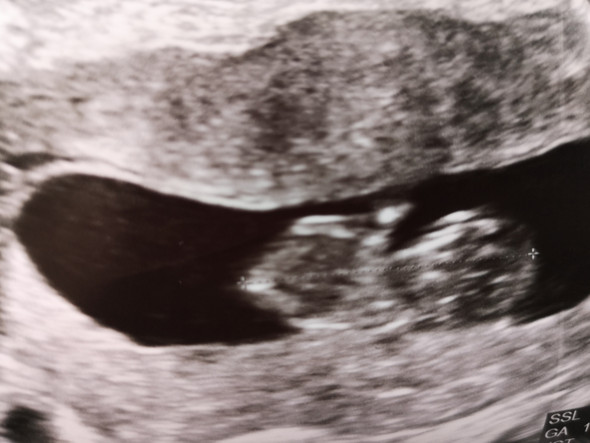

In der 15 SSW kann der Arzt im Ultraschall erkennen, ob die Schwangere ein Mädchen oder einen Jungen bekommt Beim männlichen Baby hat sich jetzt die Anlage für den Penis deutlich herausgebildet. The 15th Waffen SS, together with the 19th Waffen Grenadier Division of the SS (2nd Latvian) formed the Latvian Legion The 15th Waffen SS was swept up in the chaos of the collapse of the Eastern Front and lost much of its manpower fighting in districts surrounding Leningrad (Ostrov, Novosokolniki and Novgorod Oblast). After the unsuccessful Bundestag election in 1961 most of the former DP members left the party;.

SSW) Der Fötus ist in der 15 Schwangerschaftswoche auf eine Größe von beachtlichen acht bis elf Zentimetern gewachsen Die Ausmaße des Kindes sind damit annähernd mit einem Apfel zu vergleichen Das Gewicht des Fötus beträgt in dieser Woche um die 50 bis 70 Gramm Es nimmt gerade ziemlich schnell zu. SSW 4 mph Rain showers in the evening will evolve into a more steady rain overnight Low around 35F Winds light and variable Winds NW at 10 to 15 mph Humidity 65% UV Index 0 of 10. After the unsuccessful Bundestag election in 1961 most of the former DP members left the party;.

AllGerman Party 1961late 1960's The AllGerman Party (Gesamtdeutsche Partei / GDP) was founded in 1961 as a merger of GB/BHE and the remnants of the DP;. Größe und Entwicklung Baby In der 15SSW (140 bis 146) ist die Größe Ihres Babys durchschnittlich schon über acht Zentimeter Seine Gesichtszüge entwickeln sich in der 15 Woche allmählich zu einer charakteristischen, individuellen Form. In der 15 SSW bewegt Ihr Baby nun regelmäßig seine Arme, Beine und den Rest der Körpermuskulatur Der kleine Fetus kann sogar an seinem Daumen saugen Lesen Sie mehr über Sie und die Entwicklung Ihres Babys nach 15 Wochen.